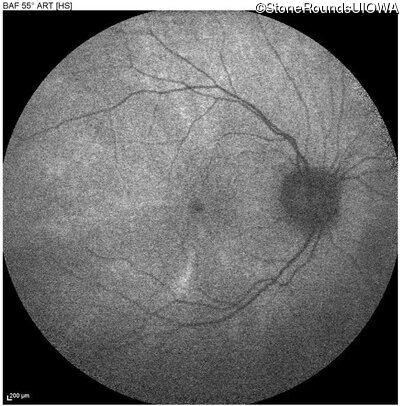

Blue Autofluorescence - Right - 20/25 -1 sc

Exemplar